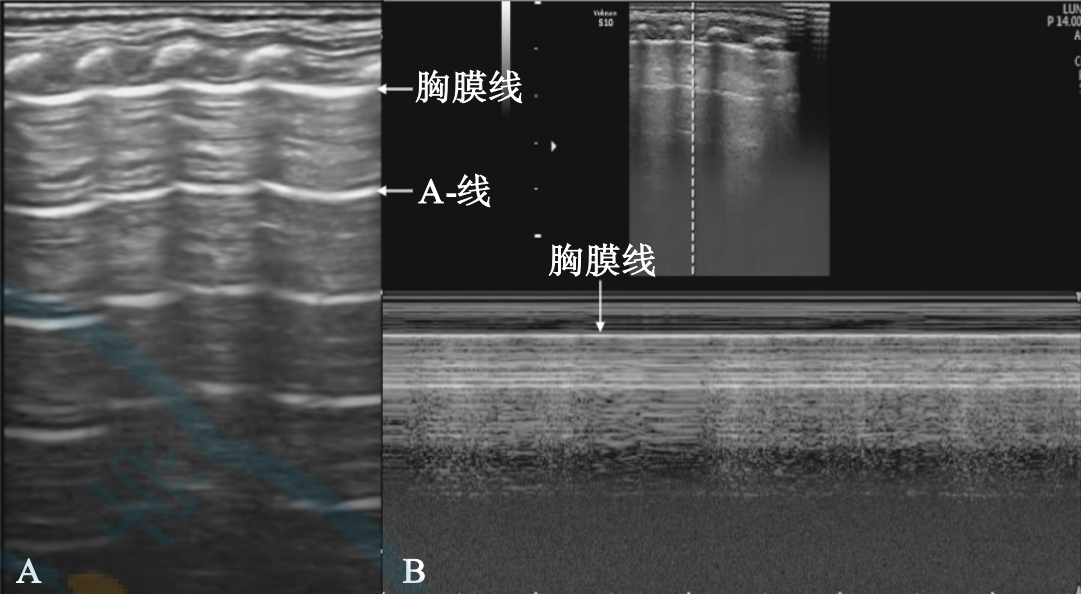

新生儿正常肺脏超声影像学检查(出自文献【1】)